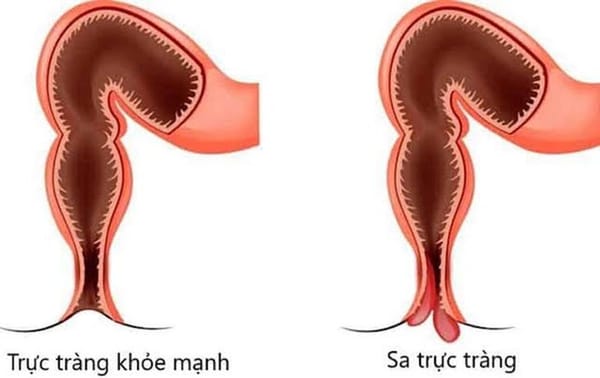

ThS.BS Hồng Quý Quân cho biết: Lồng ruột cấp tính là cấp cứu ngoại khoa thường gặp ở trẻ nhũ nhi (trẻ còn bú mẹ), xảy ra khi đoạn cuối ruột non (hồi tràng) chui qua van hồi manh tràng để vào lồng đoạn manh tràng. Do van hồi manh tràng hẹp nên các mạch máu của đoạn hồi tràng sẽ bị thắt nghẹt dẫn tới thiếu máu nếu để lâu sẽ gây hoại tử ruột.